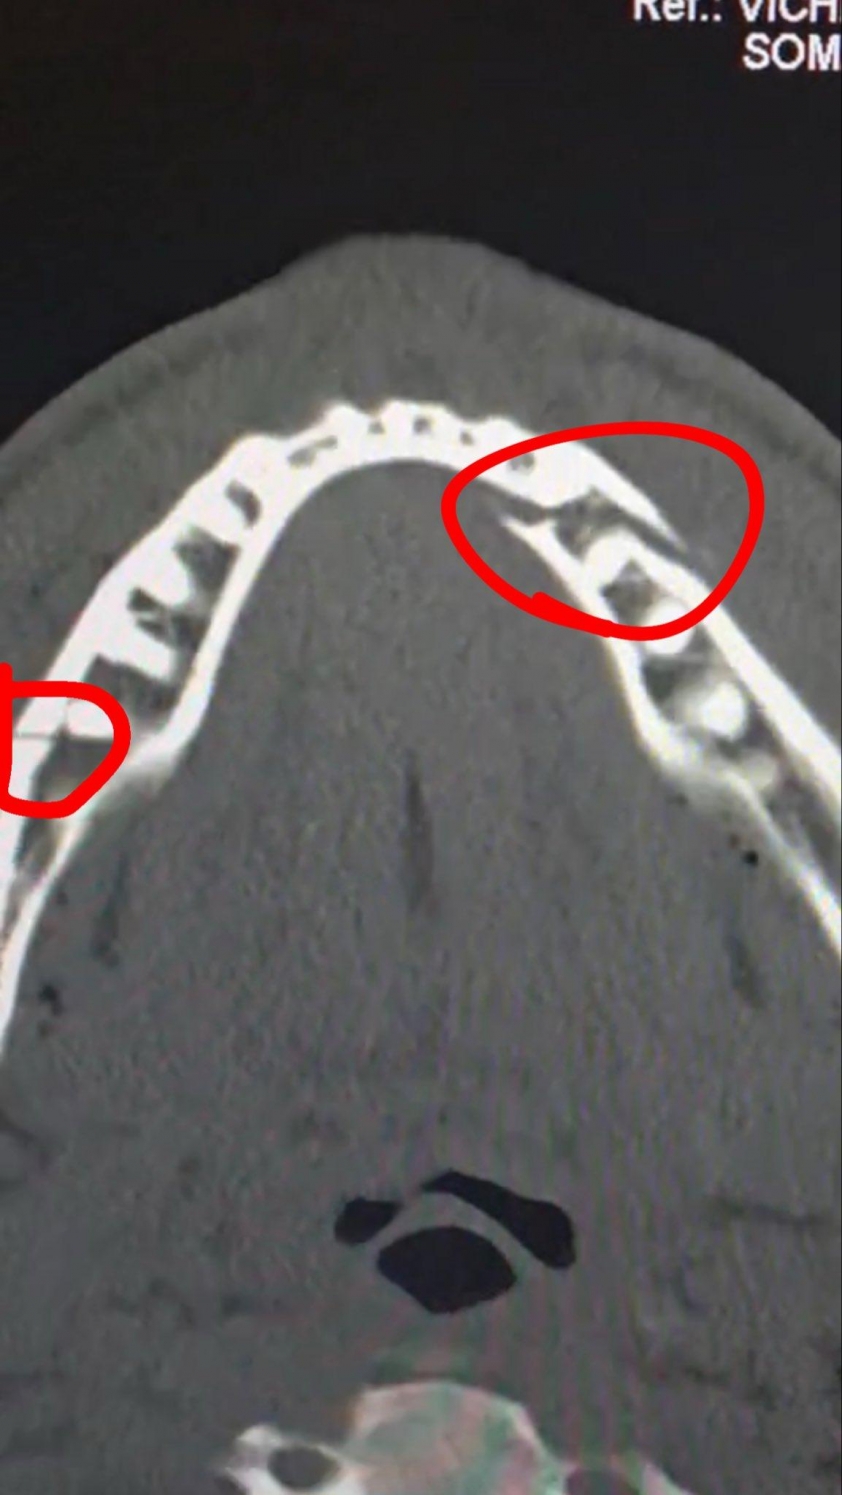

Sau nhiều hiệp kiểm soát thế trận, Joshua tung cú đấm tay phải uy lực ở hiệp 6, hạ gục Paul và kết thúc màn so găng. Ngay sau đó, Jake Paul tự lái xe tới bệnh viện để kiểm tra chấn thương vùng mặt. Kết quả chụp chiếu xác nhận anh bị gãy xương hàm. Tay đấm này sau đó đăng tải hình ảnh phim X-quang lên mạng xã hội, kèm dòng chú thích mang tính bông đùa nhưng gây chú ý: "Gãy cả hai hàm. Cho tôi đấu với Canelo Alvarez trong 10 ngày nữa".